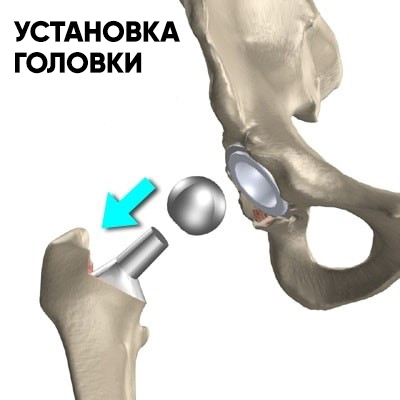

Подбирается головка требуемого размера и бедренный компонент вправляется в вертлужный. После хирург проверяет стабильность бедра и объем движений.